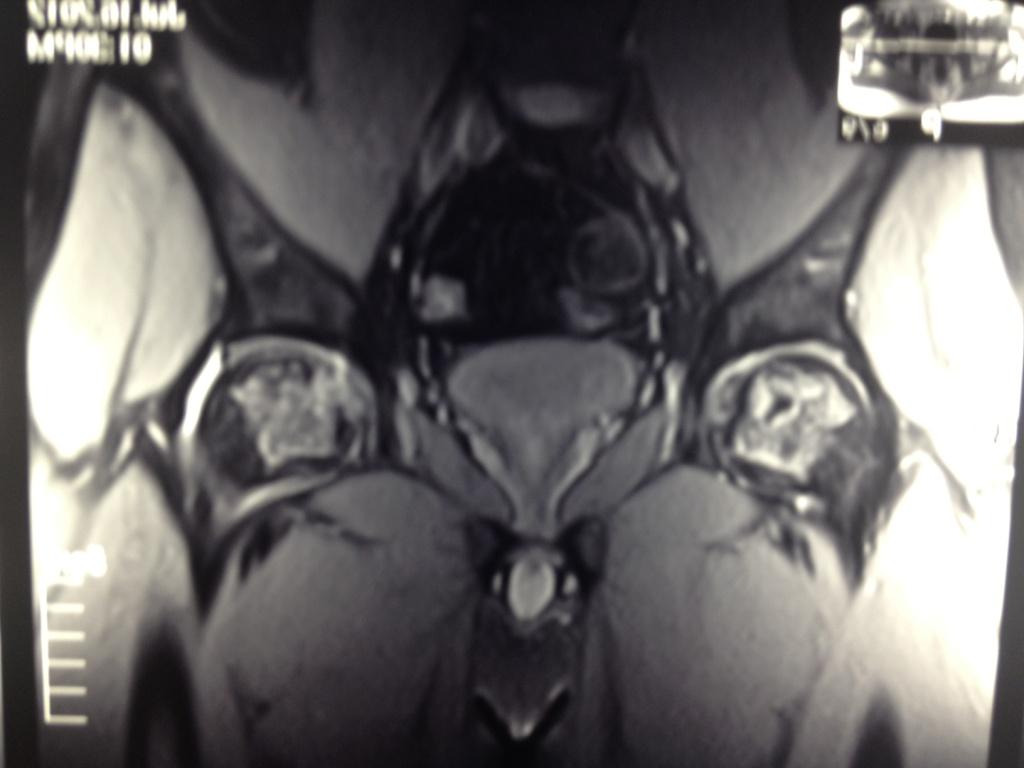

Пациента,32 лет.беспокоят боли в левом тазобедренном суставе. Болеет около 2 лет. Клинически - незначительные боли и ограничение ротации. Данные Рент, КТ, МРТ прилагаются